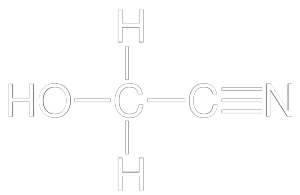

HYDROGEN

CYANIDE